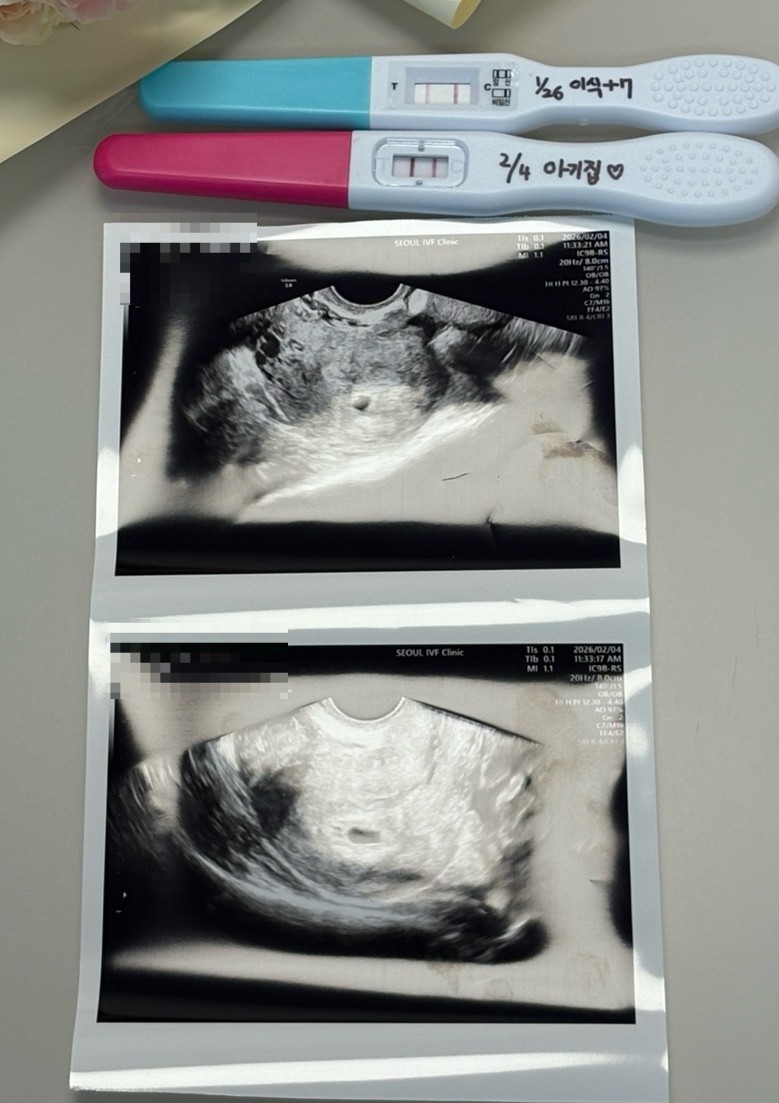

| 가슴 떨리는 임신 이야기를 공유해 주세요. | 30대 중반 동갑 부부로 2023년 7월 결혼 후 자연스럽게 아기가 찾아올 것이라 생각했지만, 시간이 지나며 쉽지 않다는 것을 알게 되었습니다. 2024년 12월부터 타 병원에서 자연임신을 시도했으나, 돌발성 난청으로 잠시 쉬어가는 시간을 가지게 되었고 그 과정에서 아이에 대한 간절함을 더욱 깨닫게 되었습니다. 이후 2025년 7월 이유정 원장님께 첫 진료를 받았고, 자연임신 시도 실패 후 고민 끝에 인공수정을 건너뛰고 시험관을 선택하게 되었습니다. 난자 채취 과정은 쉽지 않았지만 원장님을 믿고 따라간 끝에, 이식 후 1차 피검사에서 임신 소식을 듣게 되어 큰 기쁨을 느꼈습니다. |

| 치료 도중 느꼈던 가장 기뻤던 순간과 절망적인 것들은 무엇인가요? 잊지 못할 경험이 있나요? | 난자 10개 채취 후 8개 수정이 되었지만 동결배아가 2개만 나왔을 때는 절망감을 느꼈습니다. 하지만 며칠 뒤 배아가 하나 더 추가되어 3개가 되었을 때 큰 기쁨을 느꼈고, 그 포배기 배아로 임신에 성공하게 되어 더욱 의미 있는 순간으로 남았습니다. |